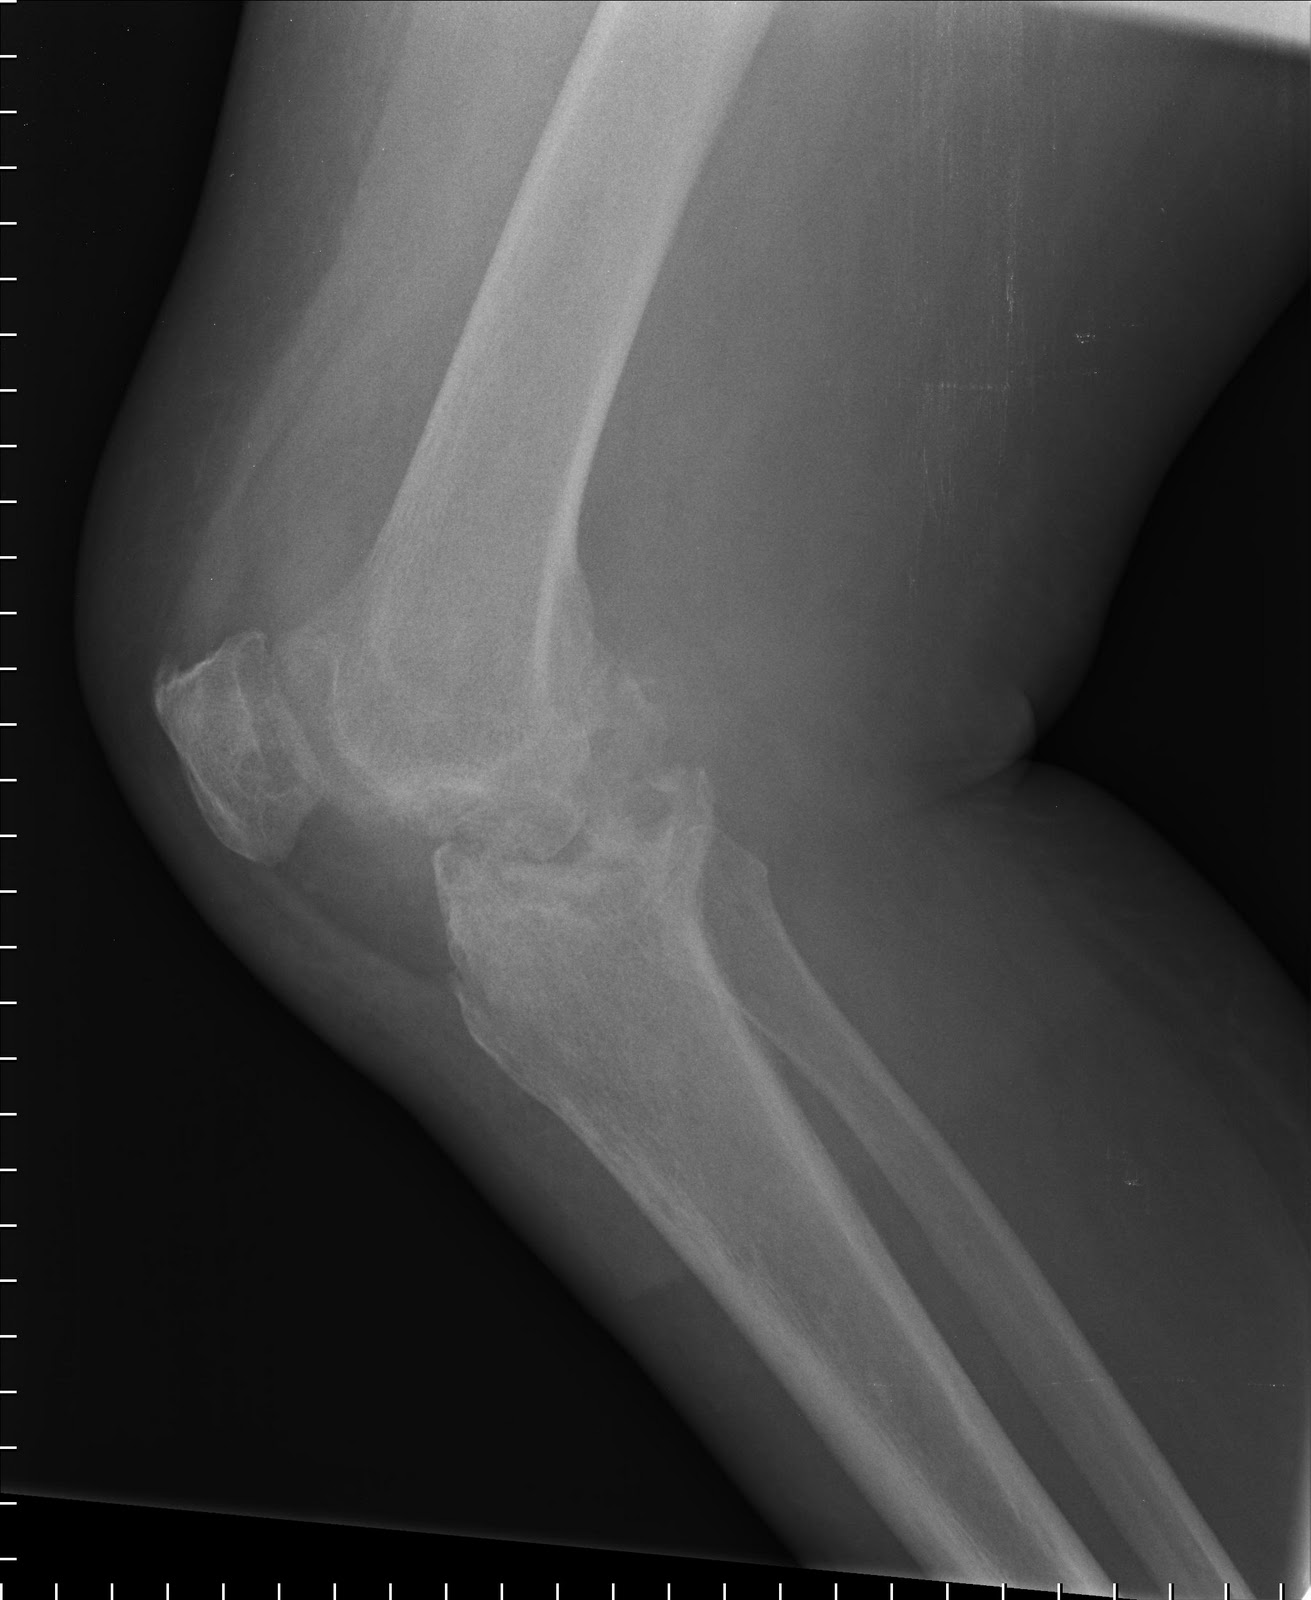

Trauma - Petrous Bone Fracture

| Longitudinal petrous bone fracture, with opacification of the mastoid air cells, and pneumocephalus. |